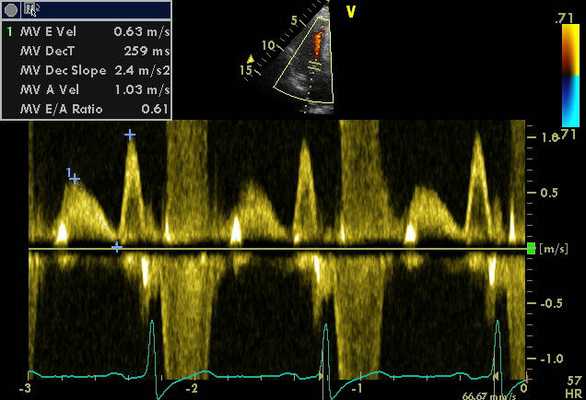

ЭхоКГ (стандартная и в режиме тканевой допплерографии) проводилась на ультразвуковой диагностической системе Vivid Five фирмы General Electric (США) секторным датчиком c частотой 3,75 МГц. Исследовалось движение продольных волокон миокарда в проекциях по длинной оси левого желудочка из верхушечного доступа. Тканевая допплерография проводилась в 4-, 3- и 2-камерной проекциях в каждом из 16 сегментов левого желудочка и в 4 точках митрального кольца: у основания заднеперегородочной, боковой, нижней и передней стенок левого желудочка. Оценивались следующие параметры.

- Пиковые миокардиальные скорости: Sm (см/с) - пиковая систолическая скорость; Em (см/с) - пиковая скорость раннего диастолического расслабления; Am (см/с) - пиковая скорость в фазу систолы предсердий.

- Временные интервалы: систолический (TRS; от вершины зубца R на ЭКГ до вершины пика Sm) и диастолический (TRE; от вершины зубца R на ЭКГ до вершины пика Em).